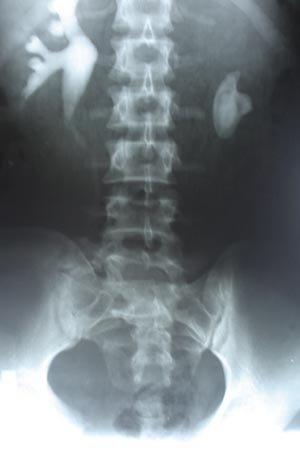

IVP staghorn calculas

It reveals a staghorn calculas on right side with absent nephrogram on right side. Left kidney shows compensatory hypertrophy.